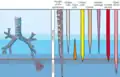

From the larynx, air moves into the trachea and down to the intersection known as the carina that branches to form the right and left primary (main) bronchi. Each of these bronchi branches into a secondary (lobar) bronchus that branches into tertiary (segmental) bronchi, that branch into smaller airways called bronchioles that eventually connect with tiny specialized structures called alveoli that function in gas exchange.

The respiratory tract is divided into the upper airways and lower airways. The upper airways or upper respiratory tract includes the nose and nasal passages, paranasal sinuses, the pharynx, and the portion of the larynx above the vocal folds (cords). The lower airways or lower respiratory tract includes the portion of the larynx below the vocal folds, trachea, bronchi and bronchioles. The lungs can be included in the lower respiratory tract or as separate entity and include the respiratory bronchioles, alveolar ducts, alveolar sacs, and alveoli.[3]

The respiratory tract can also be divided into a conducting zone and a respiratory zone, based on the distinction of transporting gases or exchanging them.

The conducting zone includes structures outside of the lungs – the nose, pharynx, larynx, and trachea, and structures inside the lungs – the bronchi, bronchioles, and terminal bronchioles. The conduction zone conducts air breathed in that is filtered, warmed, and moistened, into the lungs. It represents the 1st through the 16th division of the respiratory tract. The conducting zone is most of the respiratory tract that conducts gases into and out of the lungs but excludes the respiratory zone that exchanges gases. The conducting zone also functions to offer a low resistance pathway for airflow. It provides a major defense role in its filtering abilities.

The respiratory zone includes the respiratory bronchioles, alveolar ducts, and alveoli, and is the site of oxygen and carbon dioxide exchange with the blood. The respiratory bronchioles and the alveolar ducts are responsible for 10% of the gas exchange. The alveoli are responsible for the other 90%. The respiratory zone represents the 16th through the 23rd division of the respiratory tract.

The lower respiratory tract or lower airway is derived from the developing foregut and consists of the trachea, bronchi (primary, secondary and tertiary), bronchioles (including terminal and respiratory), and lungs (including alveoli).[8] It also sometimes includes the larynx.

The lower respiratory tract is also called the respiratory tree or tracheobronchial tree, to describe the branching structure of airways supplying air to the lungs, and includes the trachea, bronchi and bronchioles.[9]

At each division point or generation, one airway branches into two smaller airways. The human respiratory tree may consist on average of 23 generations, while the respiratory tree of the mouse has up to 13 generations. Proximal divisions (those closest to the top of the tree, such as the bronchi) mainly function to transmit air to the lower airways. Later divisions including the respiratory bronchiole, alveolar ducts, and alveoli, are specialized for gas exchange.